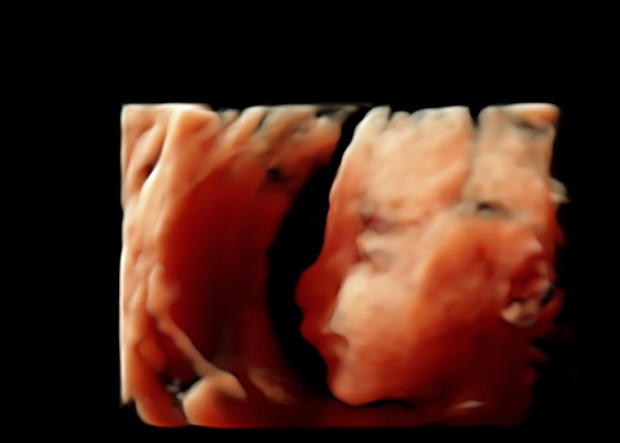

Echo 5 2eme Trimestre 22 Sa 4 Sexe Et Morphologie Enviedefraises

Echo 22 Sa Toi Moi Et Oceane Denis Aurea Et Petite Anthea Accouchement Prevu Le Fevrier 14

Echo 22sa 3d Futur Bebe 3 Es T Elle Photos Club Doctissimo

Echographie Semaines Fille Part 2 2d 3d 4d Youtube